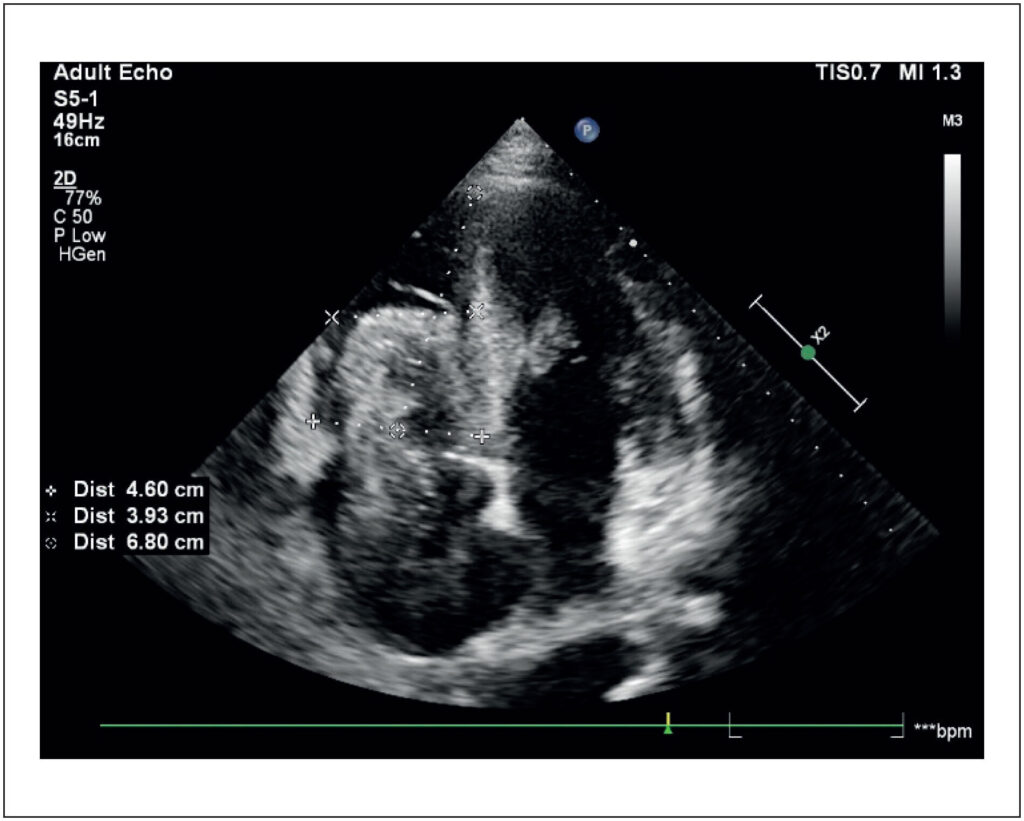

Renal cell carcinoma (RCC) is one of the most lethal cancers. It is frequently associated with the formation of tumor thrombi (TT), an intravascular extension of the tumor. Approximately 4% to 10% of patients with RCC have TT, which can reach the renal vein (10% to 18%), the inferior vena cava (4% to 23%), and, rarely, the right atrium (1%). These thrombi generally accompany advanced tumors, with distant metastases, and they reflect an aggressive biology. Treatment is challenging, especially in metastatic cases, and surgical resection is indicated in the absence of metastases. Anticoagulation remains controversial due to the neoplastic composition of TT. We report the case of a 51-year-old male patient with clear cell RCC and lung and liver metastases treated with pazopanib. The patient presented right heart failure and was diagnosed with extensive TT up to the right atrium, identified by transthoracic echocardiography. In an advanced stage, with clinical deterioration, palliative care was chosen, and the patient died within a few weeks. The diagnosis of TT is crucial to define prognosis and therapeutic strategies. Echocardiography, combined with advanced imaging techniques, plays a fundamental role in differentiating between TT and thromboembolism. This case highlights the importance of a multidisciplinary approach and technological advances for managing complex conditions such as TT, with the goals of early diagnosis and reduced complications.